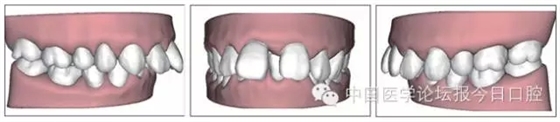

本病例為慢性牙周炎致前牙漂移、深覆(牙合)患者。本病例采用無托槽隱形矯治技術進行治療。無托槽隱形矯治器具有可摘戴、便于口腔衛(wèi)生維護和牙周治療的優(yōu)點,更適合于伴有牙周炎的錯(牙合)畸形患者的治療。 患者男,48歲,前牙有縫、前突求診。 患者面部對稱,側(cè)面觀上頜前突,下頜后縮。 口內(nèi)情況:恒牙列,24、34、44缺失,磨牙Ⅲ類關系,上牙列散隙,上前牙扇形漂移。前牙深覆(牙合)、深覆蓋??谇恍l(wèi)生較差,11與12間牙齦乳頭紅腫,多個牙探診有牙周袋形成,11松動Ⅰ度,余切牙松動(-),患者面像及口內(nèi)像如圖1、2所示。 圖1 治療前面像 圖2 治療前口內(nèi)像 全口曲面體層片(圖3)顯示,患者全牙列牙槽骨吸收;根尖片(圖4)示11近中牙槽骨角形吸收已達根尖1/3,21牙槽骨嵴頂吸收至根1/2,23牙槽骨近中骨板角形吸收至根1/2。磨牙區(qū)骨嵴頂吸收3mm。治療前頭顱側(cè)位片見圖3,治療前ODS模型見圖5。 圖4 治療前根尖片 圖5 治療前ODS模型 牙型:安氏Ⅲ類。骨型:Ⅱ類。面型:上頜前突,下頜后縮。 問題列表為:①上牙列間隙;②上切牙病理性牙移位;③前牙深覆(牙合)、深覆蓋;④24、34、44缺失;⑤慢性牙周炎。 矯治目標包括:①排齊牙列,關閉牙列間隙;②改善前牙深覆(牙合)、深覆蓋;③改善牙周狀況。 矯治設計有:①牙周基礎治療與維護。②壓低、內(nèi)收上切牙,關閉上牙列間隙。③壓低下切牙,伸長下后牙,整平Spee曲線,改善前牙覆(牙合)、覆蓋。 患者進行全口齦上潔治、齦下刮治,口腔衛(wèi)生宣教,并按牙周醫(yī)師的要求,每2~3個月行牙周檢查與治療。 牙周基礎治療結(jié)束3個月,開始隱形矯治。于14、25、35、36、45、46上粘接附件(圖6),于16、26(牙合)面粘接(牙合)墊。 圖6 ODS設計附件粘接圖示 矯治過程中注意(牙合)墊是否脫落或磨損,及時修補。 注意上前牙內(nèi)收時有無咬合干擾,及時調(diào)(牙合)。下頜前磨牙伸長到位后,磨除16、26(牙合)墊。 下頜佩戴第24步矯治器時,分別在36、37、46、47的頰、舌側(cè)粘接舌扣,矯治器上預留伸長空間,用3/16英寸、3.5盎司皮圈牽引,輔助伸長下磨牙(圖7)。 患者共戴用矯治器上頜32步,下頜26步。 矯治后,牙列間隙關閉,面型及覆(牙合)覆蓋改善。11根尖片(圖8)顯示,治療后較治療前,牙周支持組織增加,牙槽骨角形吸收區(qū)水平向縮小0.3mm,垂直向縮小0.6mm。11松動Ⅰ度,余切牙無松動。 圖8 治療后根尖片 圖9 治療后口內(nèi)像 圖10 治療后X線檢查 圖11 治療后ODS模型 正畸-牙周聯(lián)合治療對于牙周組織的影響 多學科綜合治療牙周炎患者不再是正畸治療的禁忌證。良好的牙周治療為正畸治療中的牙齒移動打下堅實基礎,而正畸治療排齊牙齒、去除(牙合)干擾,有利于牙周健康。 牙周炎患者的正畸治療必須在牙周炎癥得到控制后才能進行,否則,菌斑會隨著牙齒的移動,特別是壓低而使牙周炎癥加重。牙周炎的正確診斷、牙周炎癥控制、正畸治療中和治療后的認真維護是治療成功的關鍵。根據(jù)臨床需要,一般每2~4周做一次潔治,每3個月進行牙周評估,同時患者必須進行非常良好的日??谇恍l(wèi)生維護。 固定矯治器使得牙周檢查、潔治和日??谇恍l(wèi)生維護變得困難,隱形矯治器可自行摘戴,便于患者日常維護和牙周治療,節(jié)約時間,提高菌斑控制效果。 有臨床研究表明,對于存在(牙合)創(chuàng)傷,伴有角形吸收的患牙,經(jīng)過牙周翻瓣手術控制住牙周炎癥后,使用正畸輕力壓低患牙,可以改善牙槽骨吸收的程度,并獲得一定程度的牙周新附著。本病例切牙壓低后,原來的牙槽骨吸收有改善。 病理性牙移位 病理性牙移位(PTM)在重度牙周炎患者中的發(fā)生率為30%~50%,且常見于上前牙區(qū)。其主要由于牙周支持組織喪失尤其是骨組織的丟失,咬合因素(如后牙缺失、前牙深覆牙合、牙合創(chuàng)傷等),頰舌唇肌力量不平衡及牙周和根尖周組織炎癥所致,是牙周炎患者要求正畸治療的主要原因之一。 PTM須通過正畸、牙周聯(lián)合,有時須配合修復才能達到理想的治療效果。正畸治療通常是壓低牙齒,臨床研究表明,牙周手術配合正畸壓低可以產(chǎn)生新附著,有利于PTM牙周組織的恢復。 本病例右上中切牙牙槽骨角形吸收,在盡量保證治療前后根尖片投照角度一致的情況下,以鄰牙作為校準,在根尖片上對治療前后的骨量進行評價,治療后牙槽骨角形吸收區(qū)水平向縮小0.3 mm,垂直向縮小0.6mm。盡管根尖片并不能說明骨量改變,但從影像學上能看到骨吸收區(qū)域有所減小。 無托槽隱形矯治器矯治牙周病的優(yōu)勢 無托槽隱形矯治器具有可摘戴、便于口腔衛(wèi)生維護和牙周治療的優(yōu)點,更適合于伴有牙周炎的錯(牙合)患者的治療;同時,無托槽隱形矯治器佩戴后具有牙弓夾板和(牙合)板的作用,可有效減少側(cè)向力,有利于牙周的恢復和減輕牙齒松動;由于無托槽隱形矯治器的設計是在三維數(shù)字模型上進行的,每個矯治器移動牙齒的數(shù)量和每個牙齒的移動距離可以得到量化控制,因而可以根據(jù)患者牙槽骨水平和對矯治力的耐受情況個性化設計矯治力,并且可以根據(jù)矯治中牙齒移動情況調(diào)整后續(xù)矯治器的設計。 有關磨牙伸長 單純使用無托槽隱形矯治器同步伸長后牙比較困難。該病例先使用磨牙(牙合)墊打開咬合,通過矯治器伸長前磨牙,在前磨牙建立咬合后,磨除磨牙上的(牙合)墊,通過輔助牽引伸長磨牙,最終達到伸長后牙、整平Spee曲線的目的。 史真,主任醫(yī)師,現(xiàn)任北京黃寺整形外科醫(yī)院口腔科主任,第四軍醫(yī)大學口腔正畸學碩士,為世界正畸醫(yī)師聯(lián)盟(WFO)會員、全軍口腔醫(yī)學專業(yè)委員會委員、中華口腔正畸專業(yè)委員會委員、中華醫(yī)學美學與美容學會齒科美容學組成員、北京口腔醫(yī)學會兒童口腔專業(yè)委員會常務委員、北京口腔醫(yī)學會正畸專業(yè)委員會委員、《中華醫(yī)學美學與美容》雜志審稿專家,是我國最早開展無托槽隱形矯治技術的口腔醫(yī)師之一。